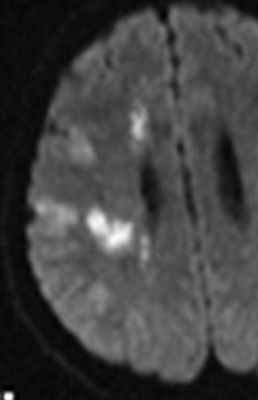

Диагностика состоит в выполнении КТ и МРТ головного мозга. Отображение крови на МРТ зависит от сроков.

МРТ головного мозга. Диффузионно-взвешенная МРТ последовательность. ОНМК в острой стадии вследствие вазоспазма.